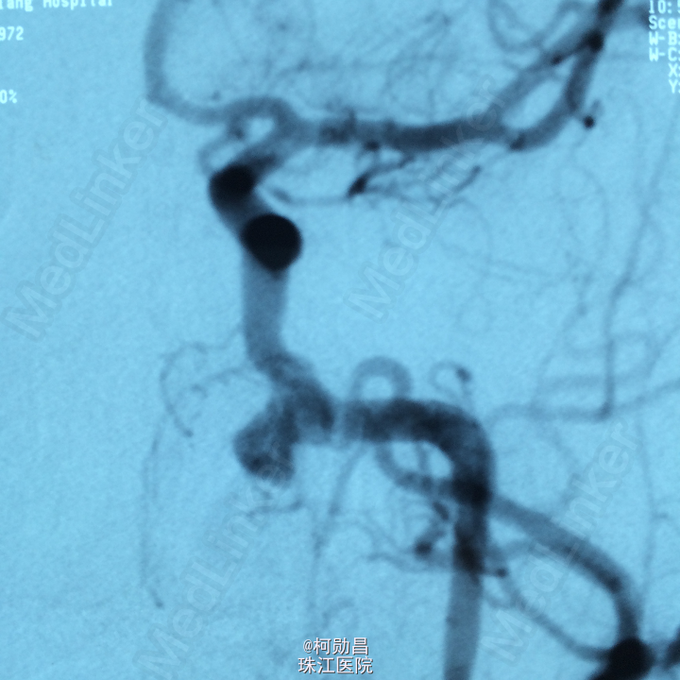

诊断:颈内动脉假性动脉瘤破裂 处理:急诊行DSA检查,提示颈内动脉海绵窦段动脉瘤形成并破裂向鼻腔引流,予血管内栓塞治疗,将动脉瘤腔堵塞,患者出血停止。